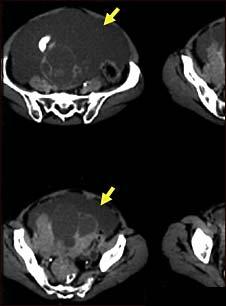

Sindromul ascitic (acumularea de lichid in abdomen)